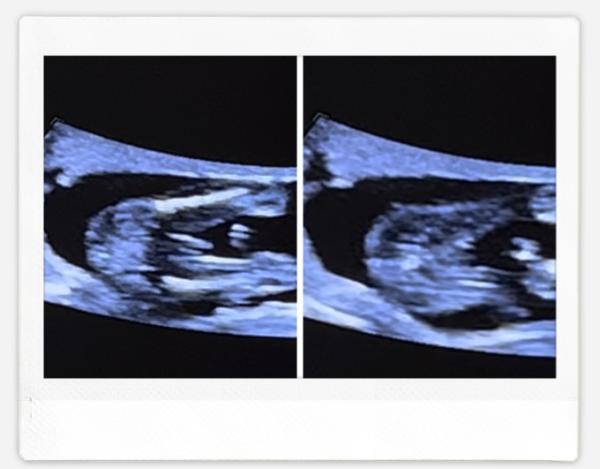

Hallo ich bin zurzeit in der 17 SSW und hatte meine Untersuchung. Alles gut soweit und die Ärztin sagt es sei zu 90% ein Junge.. Die Schwangerschaft verläuft identisch wie zur ersten (Mädchen). Wir waren auch eingestellt auf ein Mädchen und auf dem Ultraschallbild ( hab ein Video ) erkenne ich tatsächlich beide Geschlechter wodurch ich stutzig bin.. Am Ende ist es wichtig das es Gesund ist aber neugierig ist man schon.. Hat jemand Erfahrungen und was sieht ihr? Hab mir das Video wahrscheinlich 100 mal angeschaut..haha

Bild zu Junge oder doch Mädchen? (Ultraschallbild) - Schwanger - wer noch? Rund um die Schwangerschaft

Ich sehe auf beiden junge Kleiner fun facto meine erste und dritte Schwangerschaft verliefen 100 Prozent gleich, ich war mir sicher es wird wie die erste ein Mädel, tja meine Ärztin sah in der 17 Woche einen jungen und sie hat recht behalten

Also für mich sieht es wie ein Junge aus, bin aber keine Ärztin.

Ich habe drei Kinder (w,m,m) und zwei Sternchen (w,w) und bin aktuell in der 21 ssw. Bei den Mädchen war mir jede Mal sehr übel etc. , bei beiden Jungs gar nicht. Ich war ziemlich sicher, es würde wieder ein Mädchen werden. Wir bekommen aber eindeutig (NIPT und mehrfach US) einen Jungen :) Symptome sagen also wirklich wenig aus. Für mich sehen die Bilder auch nach Junge aus, vermutlich meinst du den „Schlitz“, aber das sieht bei den Hoden ähnlich aus.

Wünsche dir alles liebe für die Schwangerschaft Hatte soweit keine Symptome außer ziehen im Unterleib, Schuppen und unreine Haut wie in der ersten SS.. Ja genau die berühmten „drei Striche“ tatsächlich sah es fast genauso bei meiner Tochter aus daher der Zweifel.. werden mir wahrscheinlich erst sicherer bei dem nächsten Termin bzw. Bei der Feindiagnostik.. aber 100% sicher bei der Geburt haha Dankeschön